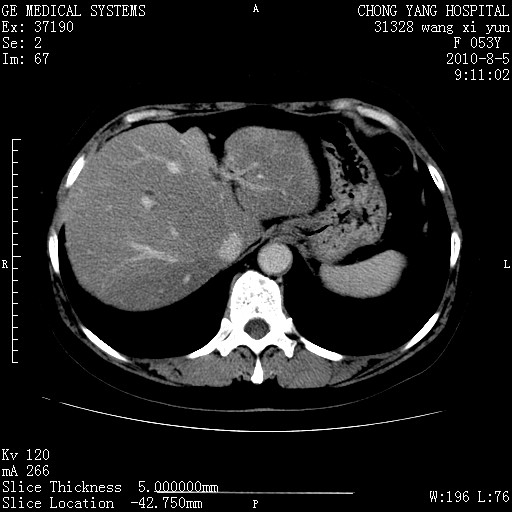

标题: CT28214:F41Y 血尿二十天,建议盆腔平扫加增强。

胆管细胞ca?

1)考虑肝左叶胆管细胞癌。2)脂肪肝。

支持胆管细胞ca。